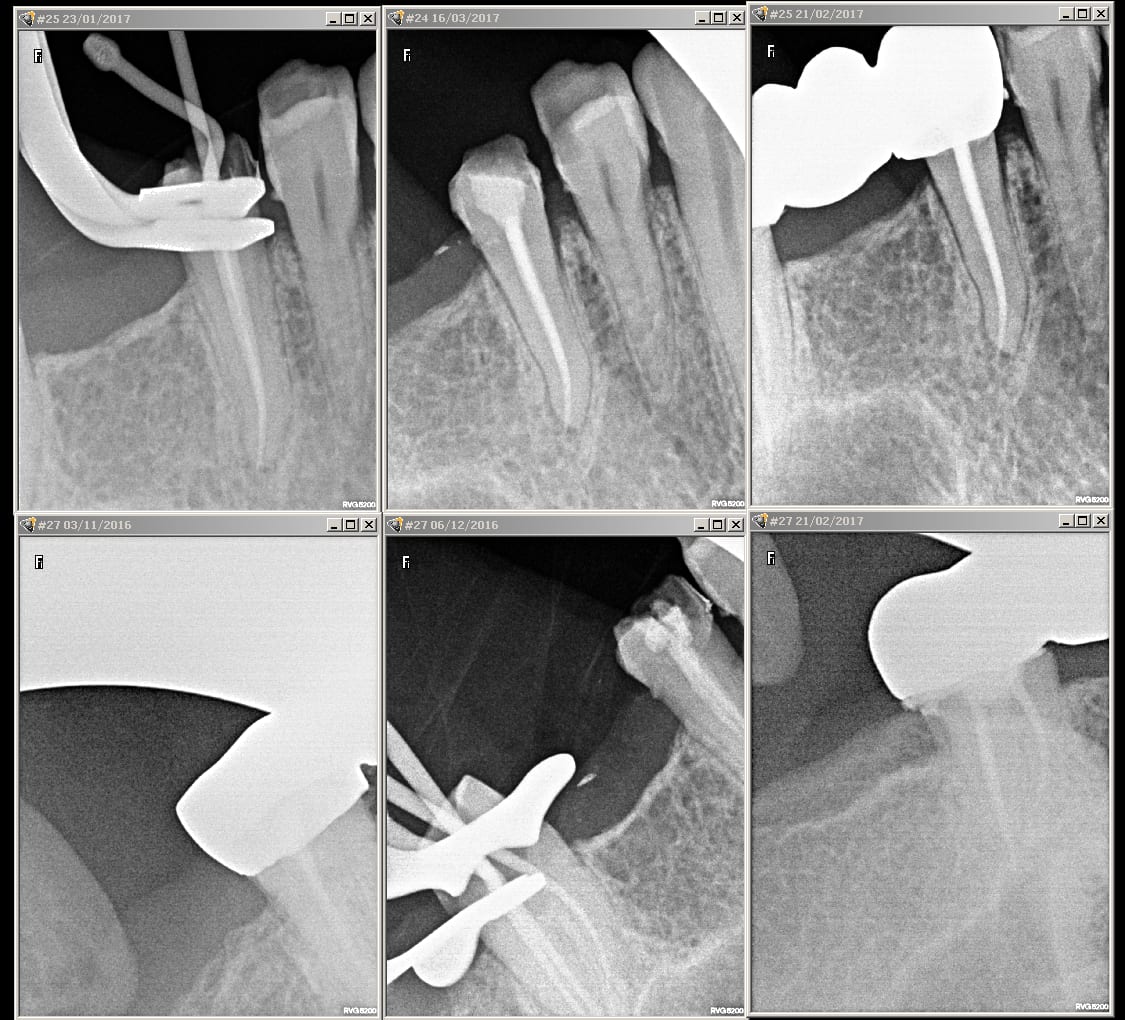

Alors voila les retros:

PS: la cavité sur la 24 est bien entendu reconstituée et la carie a été soignée le jour de mon post donc rien à voir avec les douleurs je précise.

Tu dis dans ton poste que tu as repris les traitements du secteur 20 pour ensuite dire que le bridge a une vingtaine d'années. Comment as tu fait ds ce cas pour entreprendre une rte sur 27 avec apparemment un inlay core ?... Ce que je vois sur ta pano c'est surtout 2 fractures radiculaires: une au tiers coronaire de la racine mesio vestibulaire juste à l apex du tenon l autre au tiers apical de la 25...sans parler de la grosse lésion sur la racine distale qui ressemble plus à une énorme carie sous la couronne qu'à une résorption externe.

Peut etre pour 25 un artefact? (variation brutale de densité liée au modelé osseux)?

EDIT: en regardant bien, la solution de continuité radiculaire me parait bien importante pour un artefact. La probabilité de fracture horizontale au tiers apical radiculaire est importante!

Oui je suis d'accord j'ai regardé à plusieurs reprises et c'est plus de l'ordre de la fracture ;autant sur 25 que sur la 27. Les piliers du bridge en l'état ne sont plus conservables. Pour le moment cela se manifeste par des douleurs mais d'ici quelques temps d'autres symptômes s'en suivront notamment lorsque la 27 va commencer par lâcher il va apparaître un abcès en vestibulaire juste en regard de la racine mesio vestibulaire ou peut-être en regard de l'espace inter radiculaire et non au fond du vestibule. C'est l'affaire de quelques mois. Il vaut mieux temporiser jusque là et confirmer le diagnostic. Auquel cas il faudra tout déposer et envisager l'extraction des 2 piliers.

Il n y a pas non plus de fracture que ce soit sur la 25 ou la 27, a mon avis l'image sur la 7 c'est du a la corticale, pour la 25 je l'explique pas mais j'ai les retro au cab et RAS, meme ce qui semble etre une carie en distale de la 7 be non, d'ailleurs cette radio transparence n y etait pas sur les retros... (qui sont au cab mais la c est le week end donc repos)

Des images radios quasi evidentes sur la pano qui n'apparaissent pas sur les retros surtt sur la 27 c'est qu'ils règlent très mal les appareils à Nice ! ou c'est ta rvg qui contraste mal...poste nous les retros je veux vraiment voir.